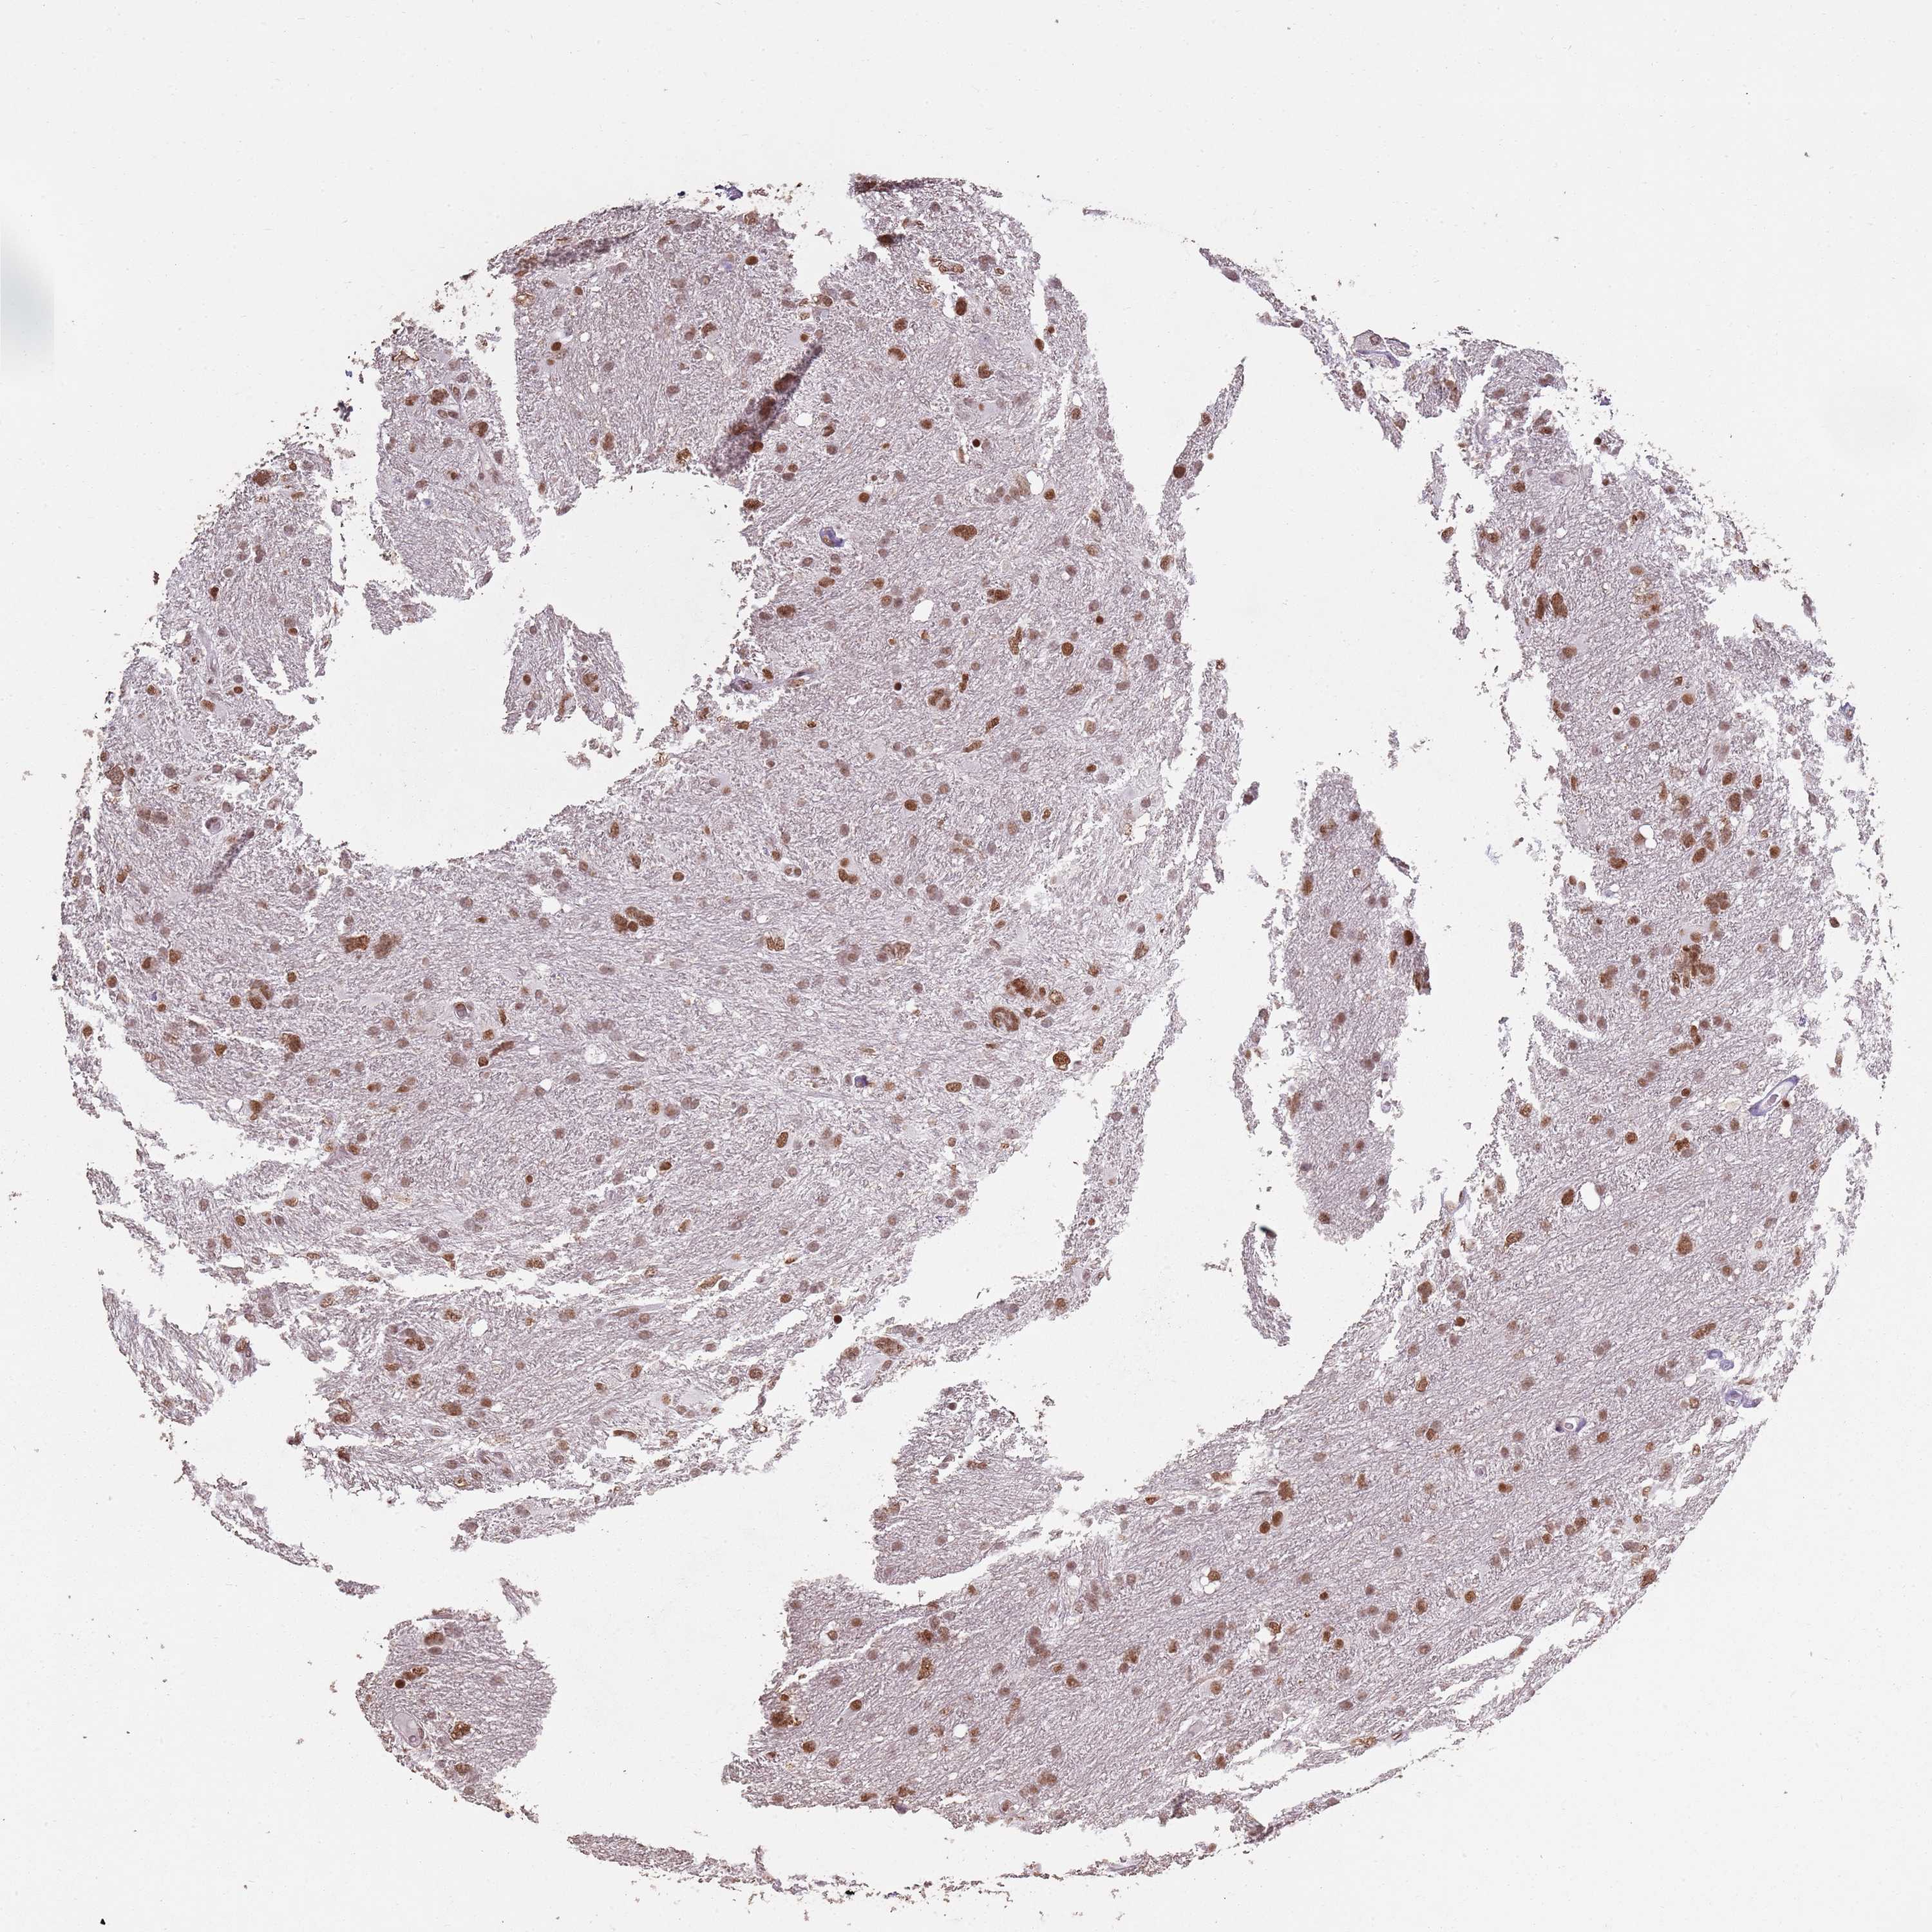

GLIOMA - Protein expressioni

A mouse-over function shows sample information and annotation data. Click on an image to view it in a full screen mode. Samples can be filtered based on level of antibody staining by selecting one or several of the following categories: high, medium, low and not detected. The assay and annotation is described here.

Note that samples used for immunohistochemistry by the Human Protein Atlas do not correspond to samples in the TCGA dataset.

Antibody stainingi

Antibody staining in the annotated cell types in the current human tissue is reported as not detected, low, medium, or high, based on conventional immunohistochemistry profiling in selected tissues. This score is based on the combination of the staining intensity and fraction of stained cells.

Each image is clickable and will lead to virtual microscopy that enables deeper exploration of all samples and also displays staining intensity scores, fraction scores and subcellular localization as well as patient and tissue information for each sample.

Antibody HPA039634

Antibody HPA048127

Staining

High

Medium

Low

Not detected

Intensity

Strong

Moderate

Weak

Negative

Quantity

>75%

75%-25%

<25%

None

Location

Nuclear

Cytoplasmic/membranous

Cytoplasmic/membranous,nuclear

Glioma, malignant, High grade

Glioma, malignant, Low grade